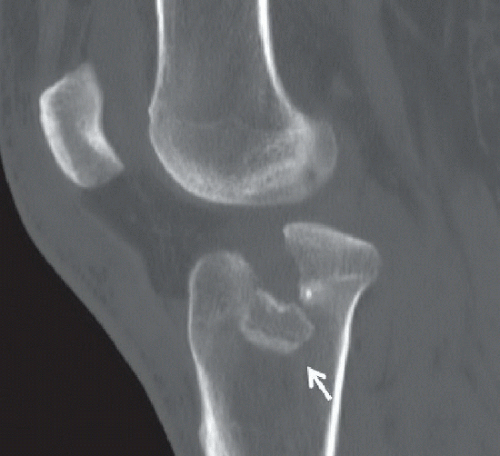

27+ Tibial Plateau X Ray Anatomy. Tibial plateau fractures signify periarticular fractures of the proximal tibia frequently associated with soft tissue injuries affecting knee stability. Normally, the tibial plateau should be visible and palpable in front of the medial and lateral femoral condyles translation of the tibial plateau to a position posterior to the femoral condyles indicates complete disruption of 15.3.1 anatomy.

Epos C 2528 from epos.myesr.org Z tibial plateau view angling the tube 15 degree cephalad provides tangential view of tibial plateau. Fractures involving the medial tibial plateau may be associated with higher incidences of peroneal nerve or popliteal neurovascular. Motor vehicle accidents account for the majority of these fractures in younger individuals, but elderly patients with osteopenic bone may experience these after a simple fall.

Tibial plateau fractures range from very small fractures, which are only seen on mri scans, to those which involve a significant injury which results in have you sustained a tibial plateau fracture? Tibial plateau fractures are complex injuries of the knee. Tibial plateau and tibial eminence avulsion fracture arthroscopic treatment 2015 p01.jpg 567 × 189; Thus anterior tibial plateau fractures may be occult on ap projections.